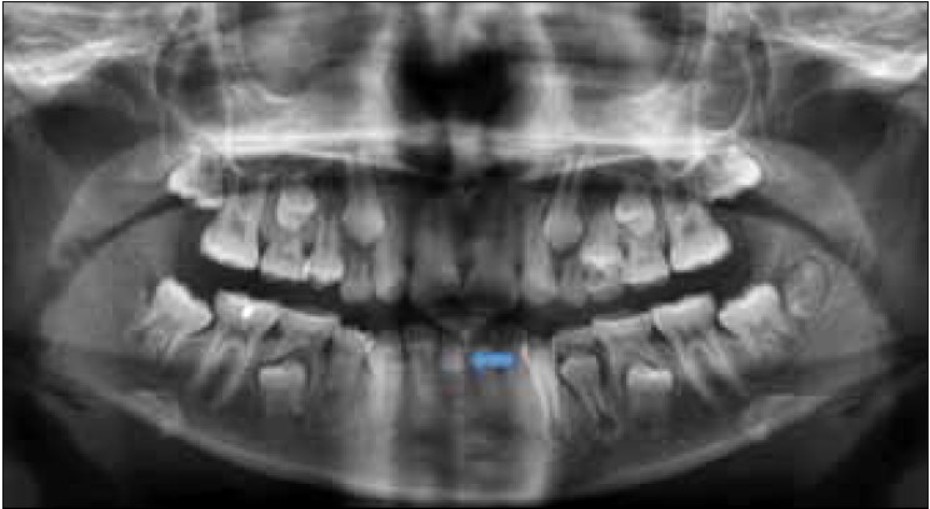

BELOW ARE X-RAYS OF ACTUAL PATIENTS

There is evidence of hereditary factors along with some evidence of environmental factors leading to this condition. While a single excess tooth is relatively common, multiple hyperdontia is rare in people with no other associated diseases or syndromes. Many supernumerary teeth never erupt, but they may delay eruption of nearby teeth or cause other dental or orthodontic problems. Molar-type extra teeth are the rarest form. Dental x-rays are often used to diagnose hyperdontia.

It is suggested that supernumerary teeth develop from a third tooth bud arising from the dental lamina near the regular tooth bud or possibly from splitting the regular tooth bud itself. Supernumerary teeth in deciduous (baby) teeth are less common than in permanent teeth.

When classified by position, a supernumerary tooth may be referred to as a mesiodens, a paramolar, or a distomolar.

The most common supernumerary tooth is a mesiodens, which is a malformed, peg-like tooth that occurs between the maxillary central incisors.

Fourth and fifth molars that form behind the third molars are another kind of supernumerary teeth.